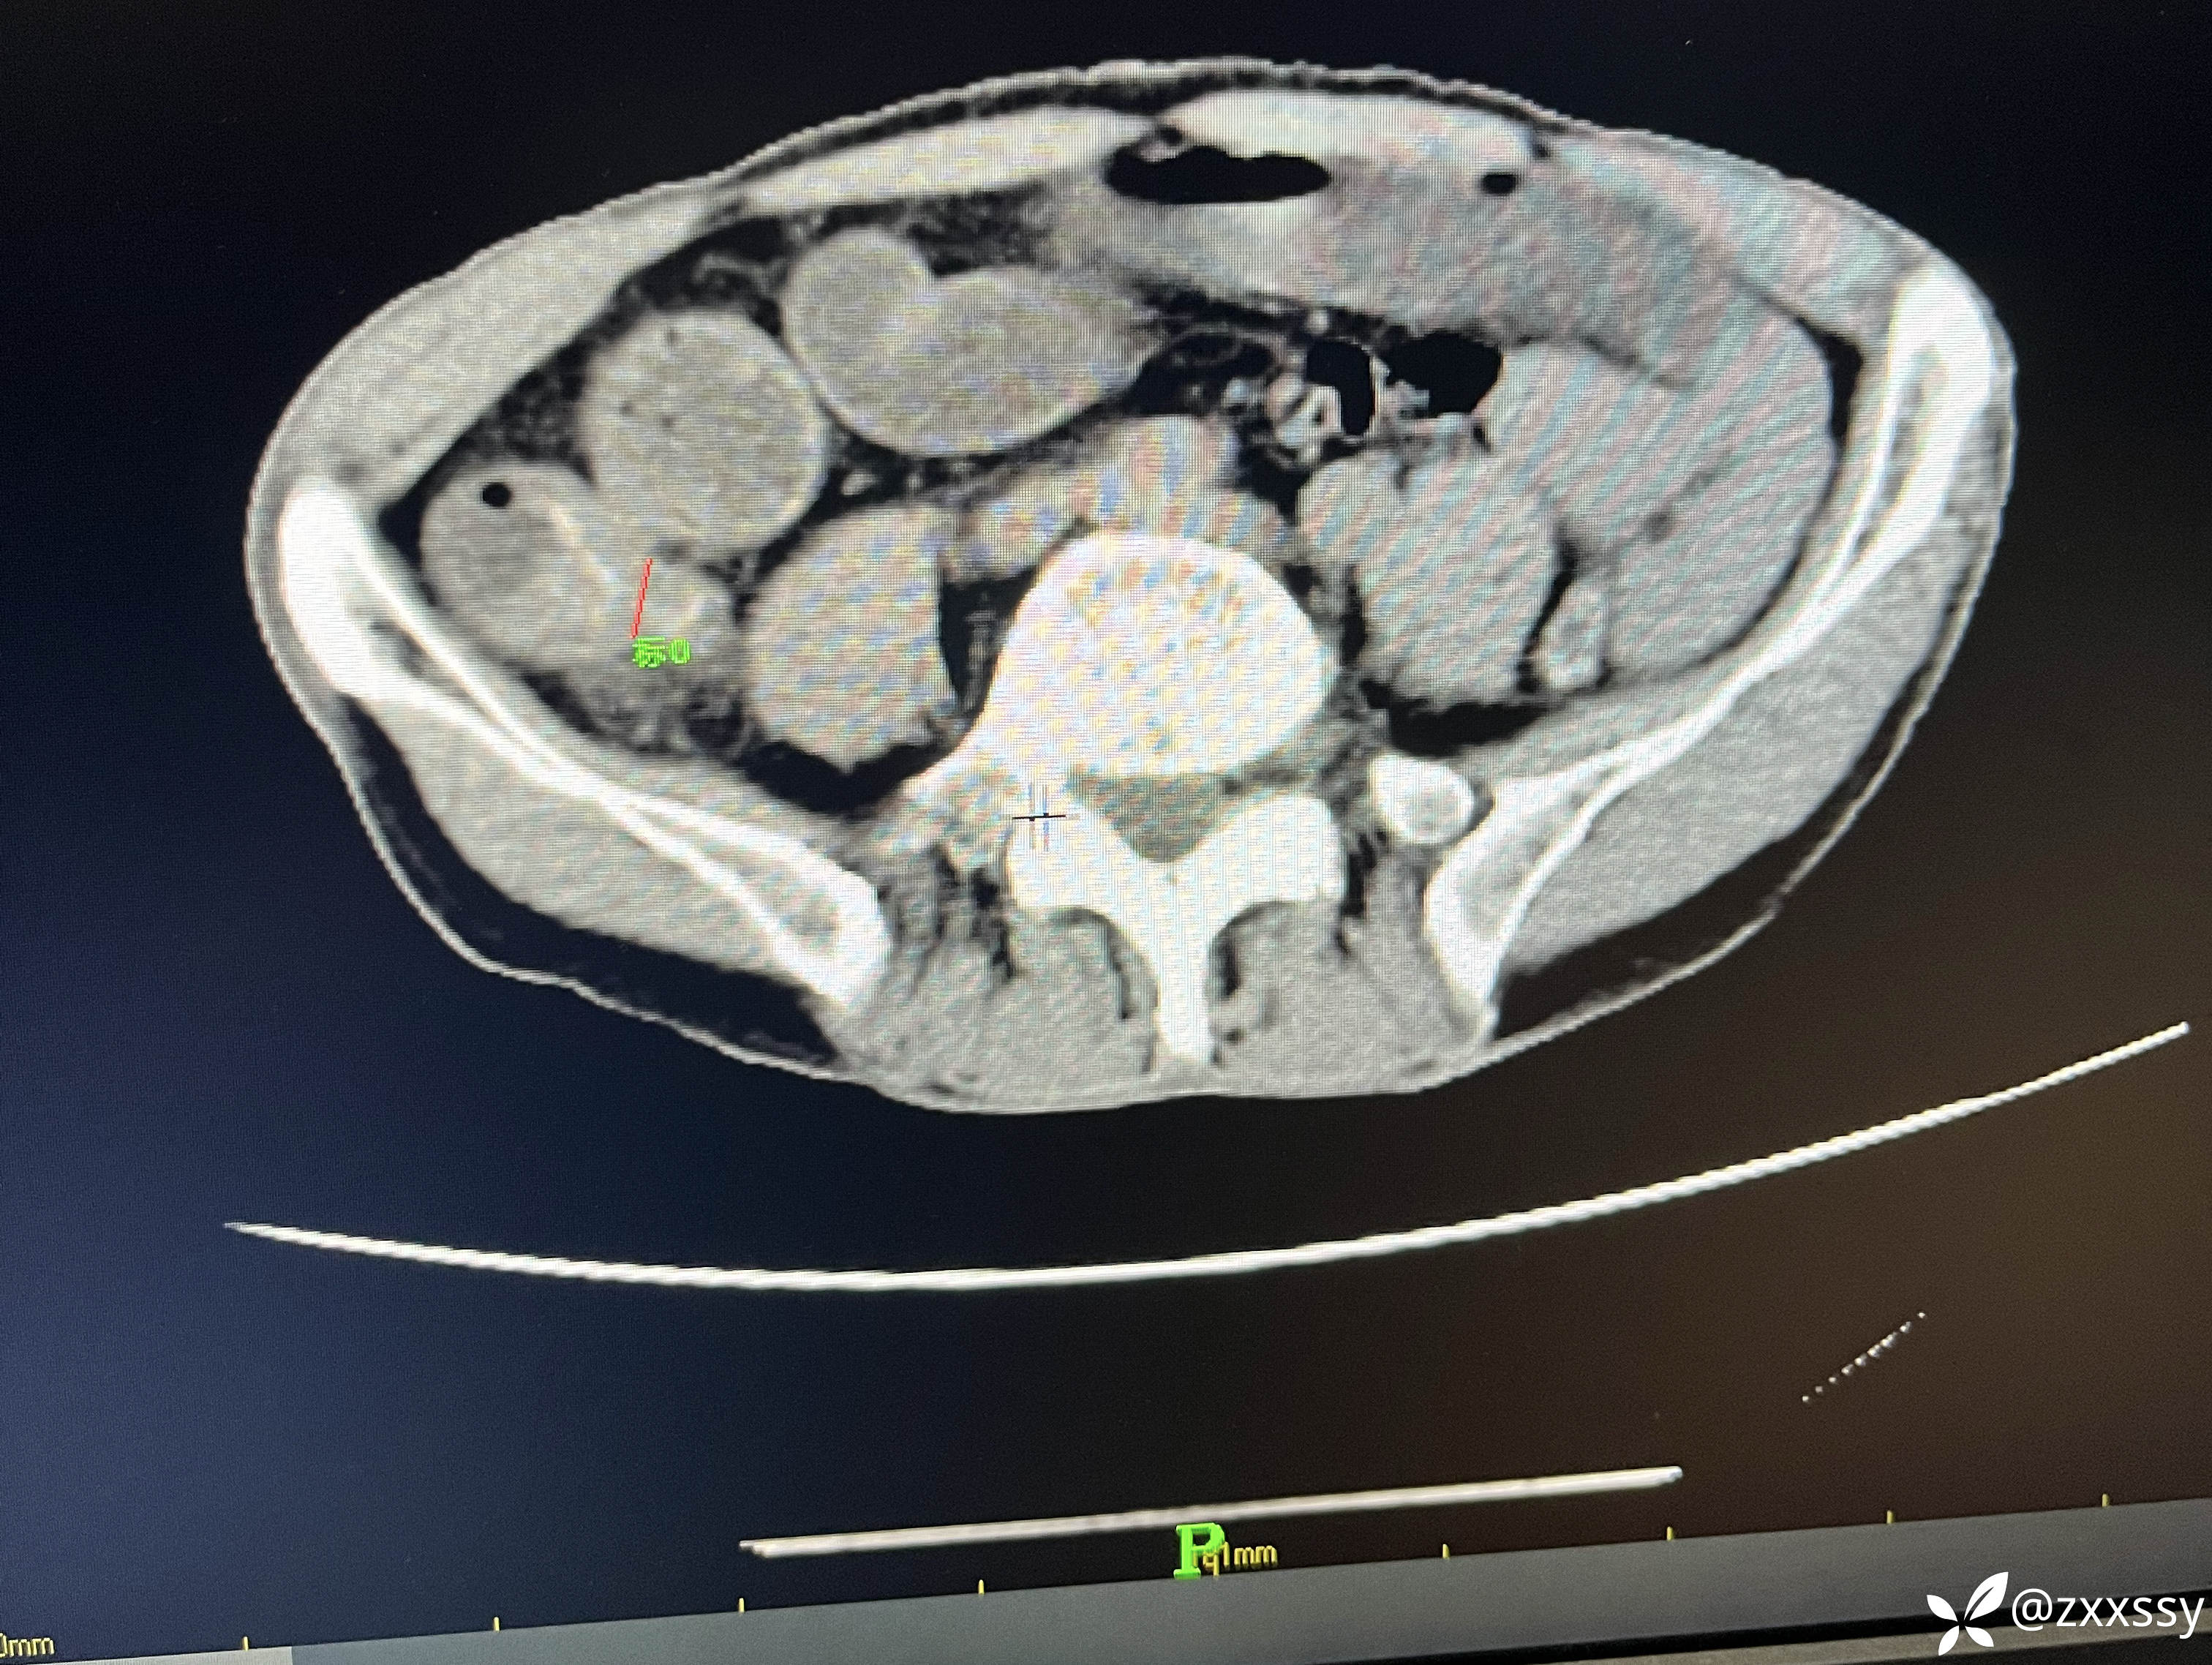

阑尾尖端粪石

临床诊断:1.急性阑尾炎并粪石形成;2.小肠梗阻;3,回盲部管璧不规则增后,周围淋巴结多发(回盲部肿瘤?);4.盆腹腔积液。